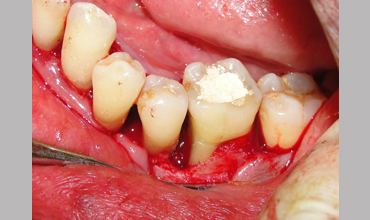

NON SURGICAL MANAGEMENT OF ENDODONTIC LESION AND SURGICAL MANAGEMENT OF PERIODONTIC LESION